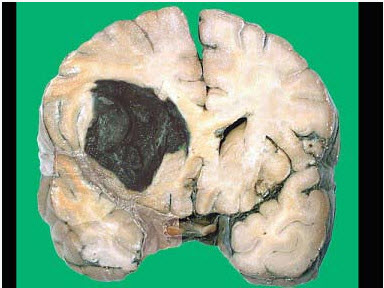

252、单项选择题

长期慢性肝淤血会导致肝内纤维结缔组织增生,肝脏质地变硬,形成淤血性肝硬化。

淤血性肝硬化镜下如图所示,有关该病变叙述错误的是()

A.肝小叶改建不明显

B.肝窦扩张淤血

C.汇管区内纤维结缔组织增生

D.假小叶形成

E.窦周细胞增生并可转化成肌成纤维细胞

257、单项选择题

该病变多见于哪种疾病()

A.左心衰竭

B.右心衰竭

C.血吸虫病

D.病毒性肝炎

E.以上均不是